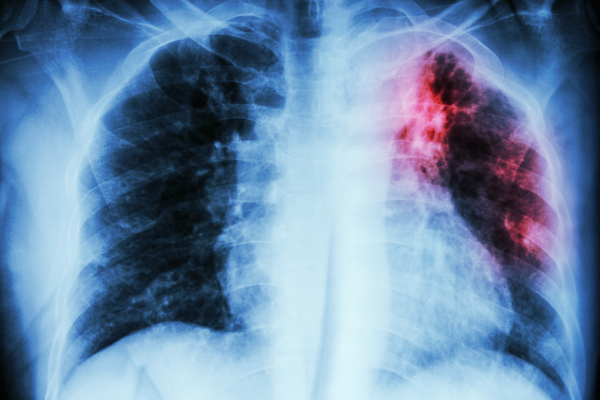

Immune and metabolic mechanisms that increase an individual’s susceptibility to develop TB disease is a research focus of Texas Biomedical Research Institute’s Executive Vice President for Research. Dr. Turner studies the changes that take place in the immune system during the natural aging process and how those changes can influence both innate and adaptive immune function when infected with M. tuberculosis (M.tb). An additional area of research in Dr. Turner’s laboratory is the use of different mouse strains to better model immune responses in humans. By doing so, her team has defined a major role for an immune-suppressive cytokine, interleukin 10, in TB susceptibility.